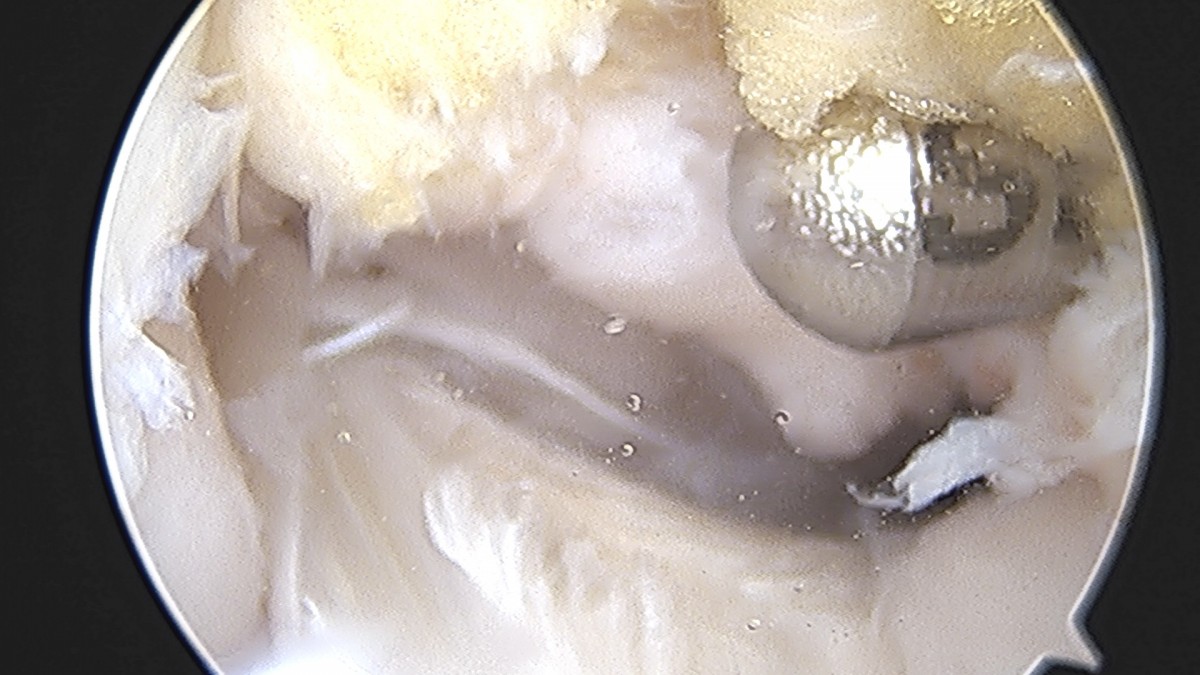

이재상원장님 무릎 반월상 연골판 절제술 박대O 환자

dae765e4d9ac96aee867c9d6292d8784_1758005045_8709.jpg